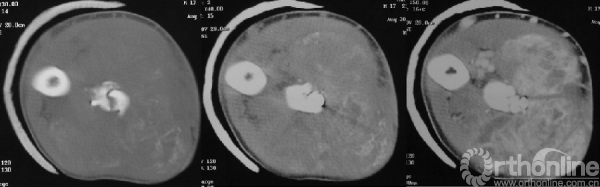

影像学检查(入院时)

图14-7 入院时X线平片正侧位(第一次术后3个月)

图14-8 入院时CT轴位骨窗、软组织窗、软组织增强窗(第一次术后3个月)

体格检查(入院时)

右前臂明显肿胀,可见多处手术疤痕,可触及肿物,质硬韧,边界不清,无活动度,可及压痛,局部皮色暗红,皮温稍高,未见破溃及静脉曲张。右肘关节及腕关节活动不受限。

浸润灶及新生软骨,但缺乏明显异型性及间变的肿瘤组织,诊断恶性细胞学证据不充足,结合临床倾向恶性成骨性肿瘤分化较好区域。

穿刺病理

间变的肿瘤细胞,富于血窦结构,细胞间见骨样组织,结合临床、影像学,初步考虑骨肉瘤的可能性大。